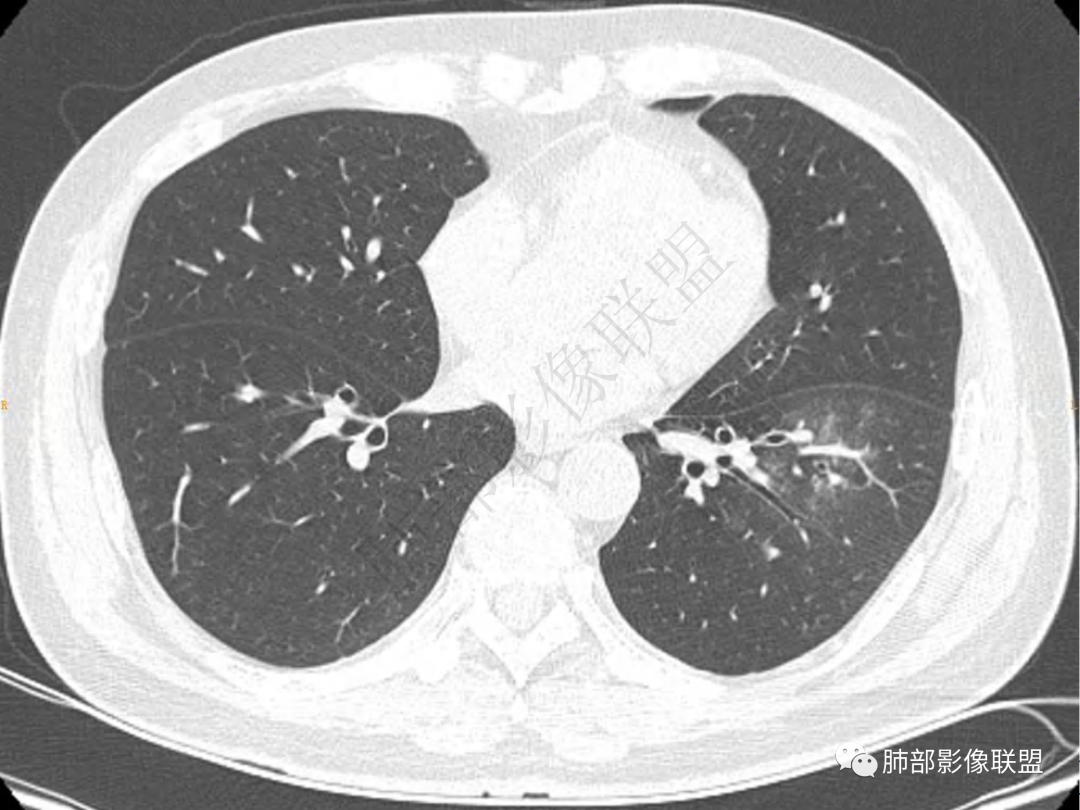

1.中年男性,咳嗽咳痰20余天,间断咯血2周

2.左肺下叶团片影,跨背段及内前基底段,实性部分类椭圆形,密度不甚均匀,可见毛刺及棘状突起,未见典型分叶及胸膜凹陷。病灶上下缘可见相应肺段支气管旁进侧出,管壁轻度增厚,未见狭窄阻塞。

3.周边较大范围磨玻璃影,边界相当模糊,小叶增厚明显。注意叶裂另一侧、左肺舌段亦可见磨玻璃影及增厚的小叶间隔。未见明确卫星病灶。